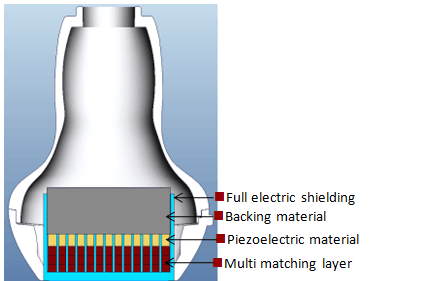

Датчики на основе технологии 3T

Датчики обеспечивают увеличение пропускной способности изображения и эффективности передачи.

Данная технология обеспечивает повышение чувствительности, увеличение пропускной способности, а также улучшение соотношения сигнал/шум

Технология total-cut предназначена для снижения уровня переходных шумов, улучшения направленности, а также повышения латерального разрешения

Терморегулирующая конструкция обеспечивает улучшенную передачу акустического сигнала